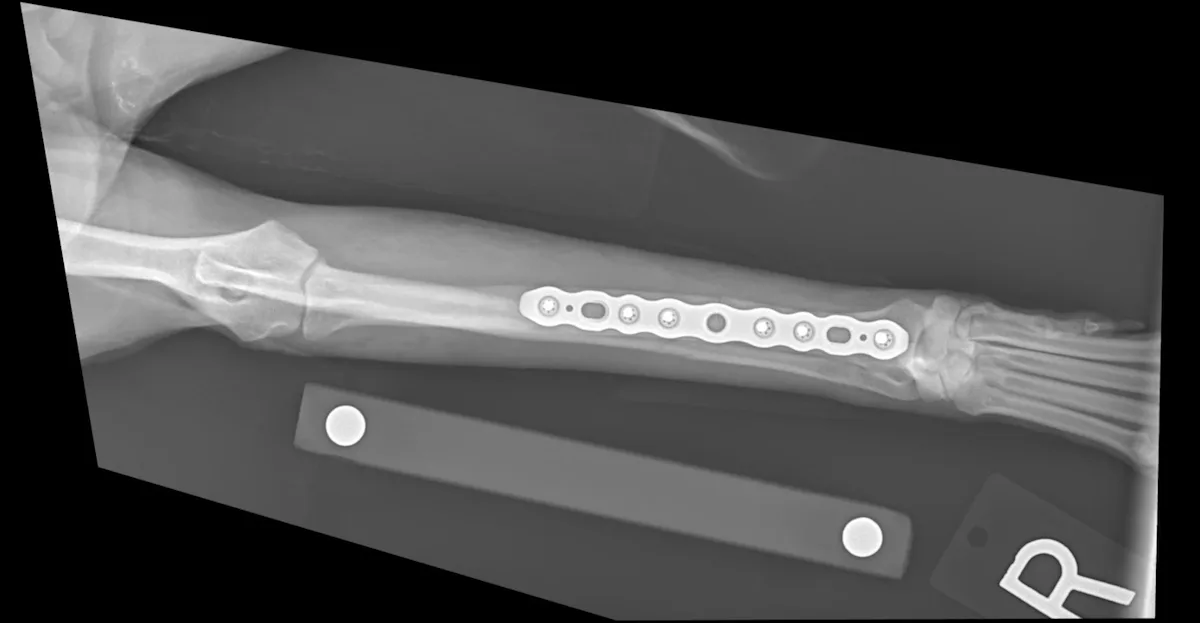

Orthopedics

Expand your knowledge on the latest in veterinary orthopedics to better provide accurate diagnoses and effective treatment.

Does your practice have the right tools in place to tackle the fractures that walk through your door? Discover 4 key tool types to help make fracture repair more achievable in general practice.